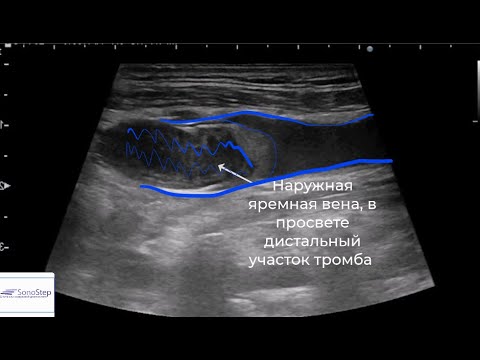

Узи вен домодедово 87 фотографий